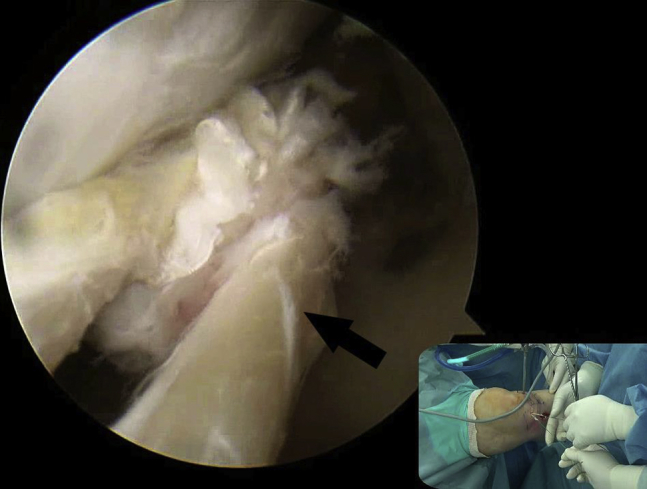

Fig 2.

Viewing from the anterolateral portal, the sharp tip of the suture hook with PDS is advanced to the torn posterior horn via the anteromedial portal. Then, the torn posterior horn is penetrated by the sharp tip of the suture hook 5-8 mm medial to the torn edge (black arrow) in a vertical direction on the left knee with valgus force at extension. (PDS, polydioxanone.)